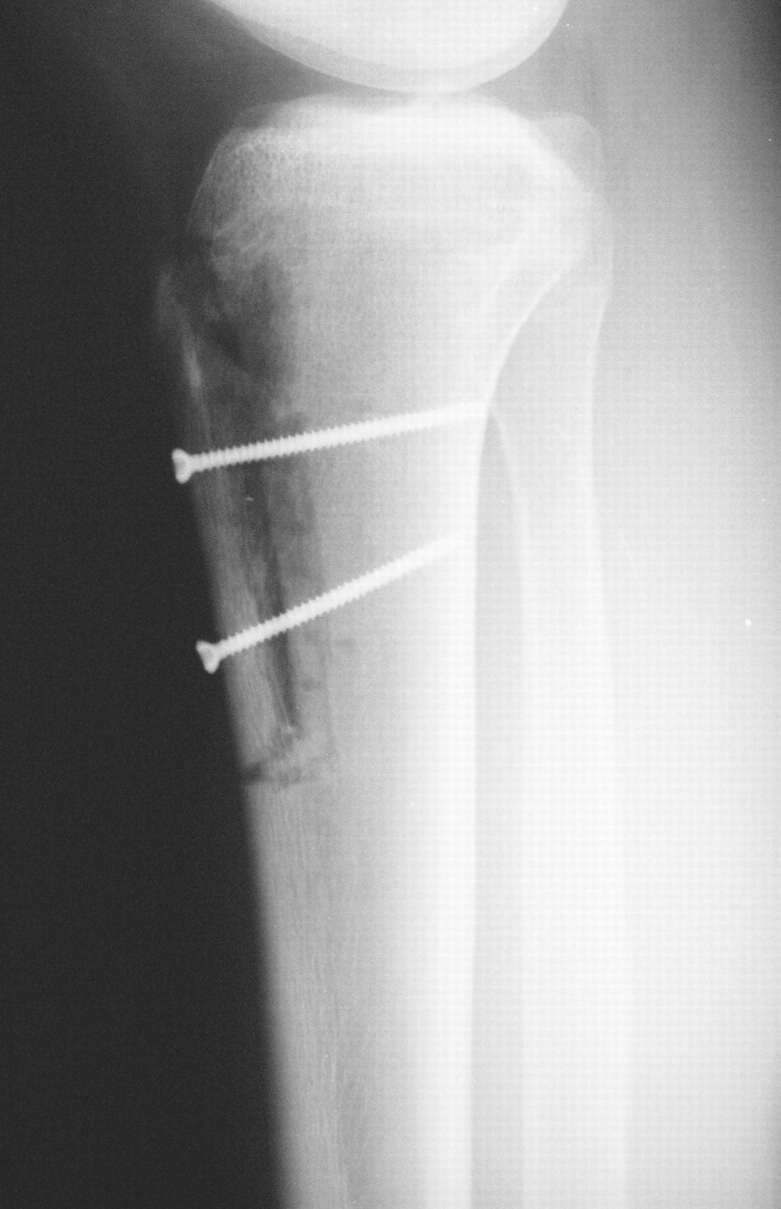

The complications of this surgery include painful hardware, delayed union, thrombosis associated with the wound vein, sensory deficit, clinical nonunion, delayed motion range. Not only that, but its complications also include a damaged screw, fascial hernia, tibial fracture, dysfunction of quadriceps, or hematoma.

The complication of the damaged screw got eliminated right after the operation of the joint. However, there are usually no cases of the affected individuals which are known to cause complications such as any particular syndrome, a pulmonary embolism, or infection of any kind.